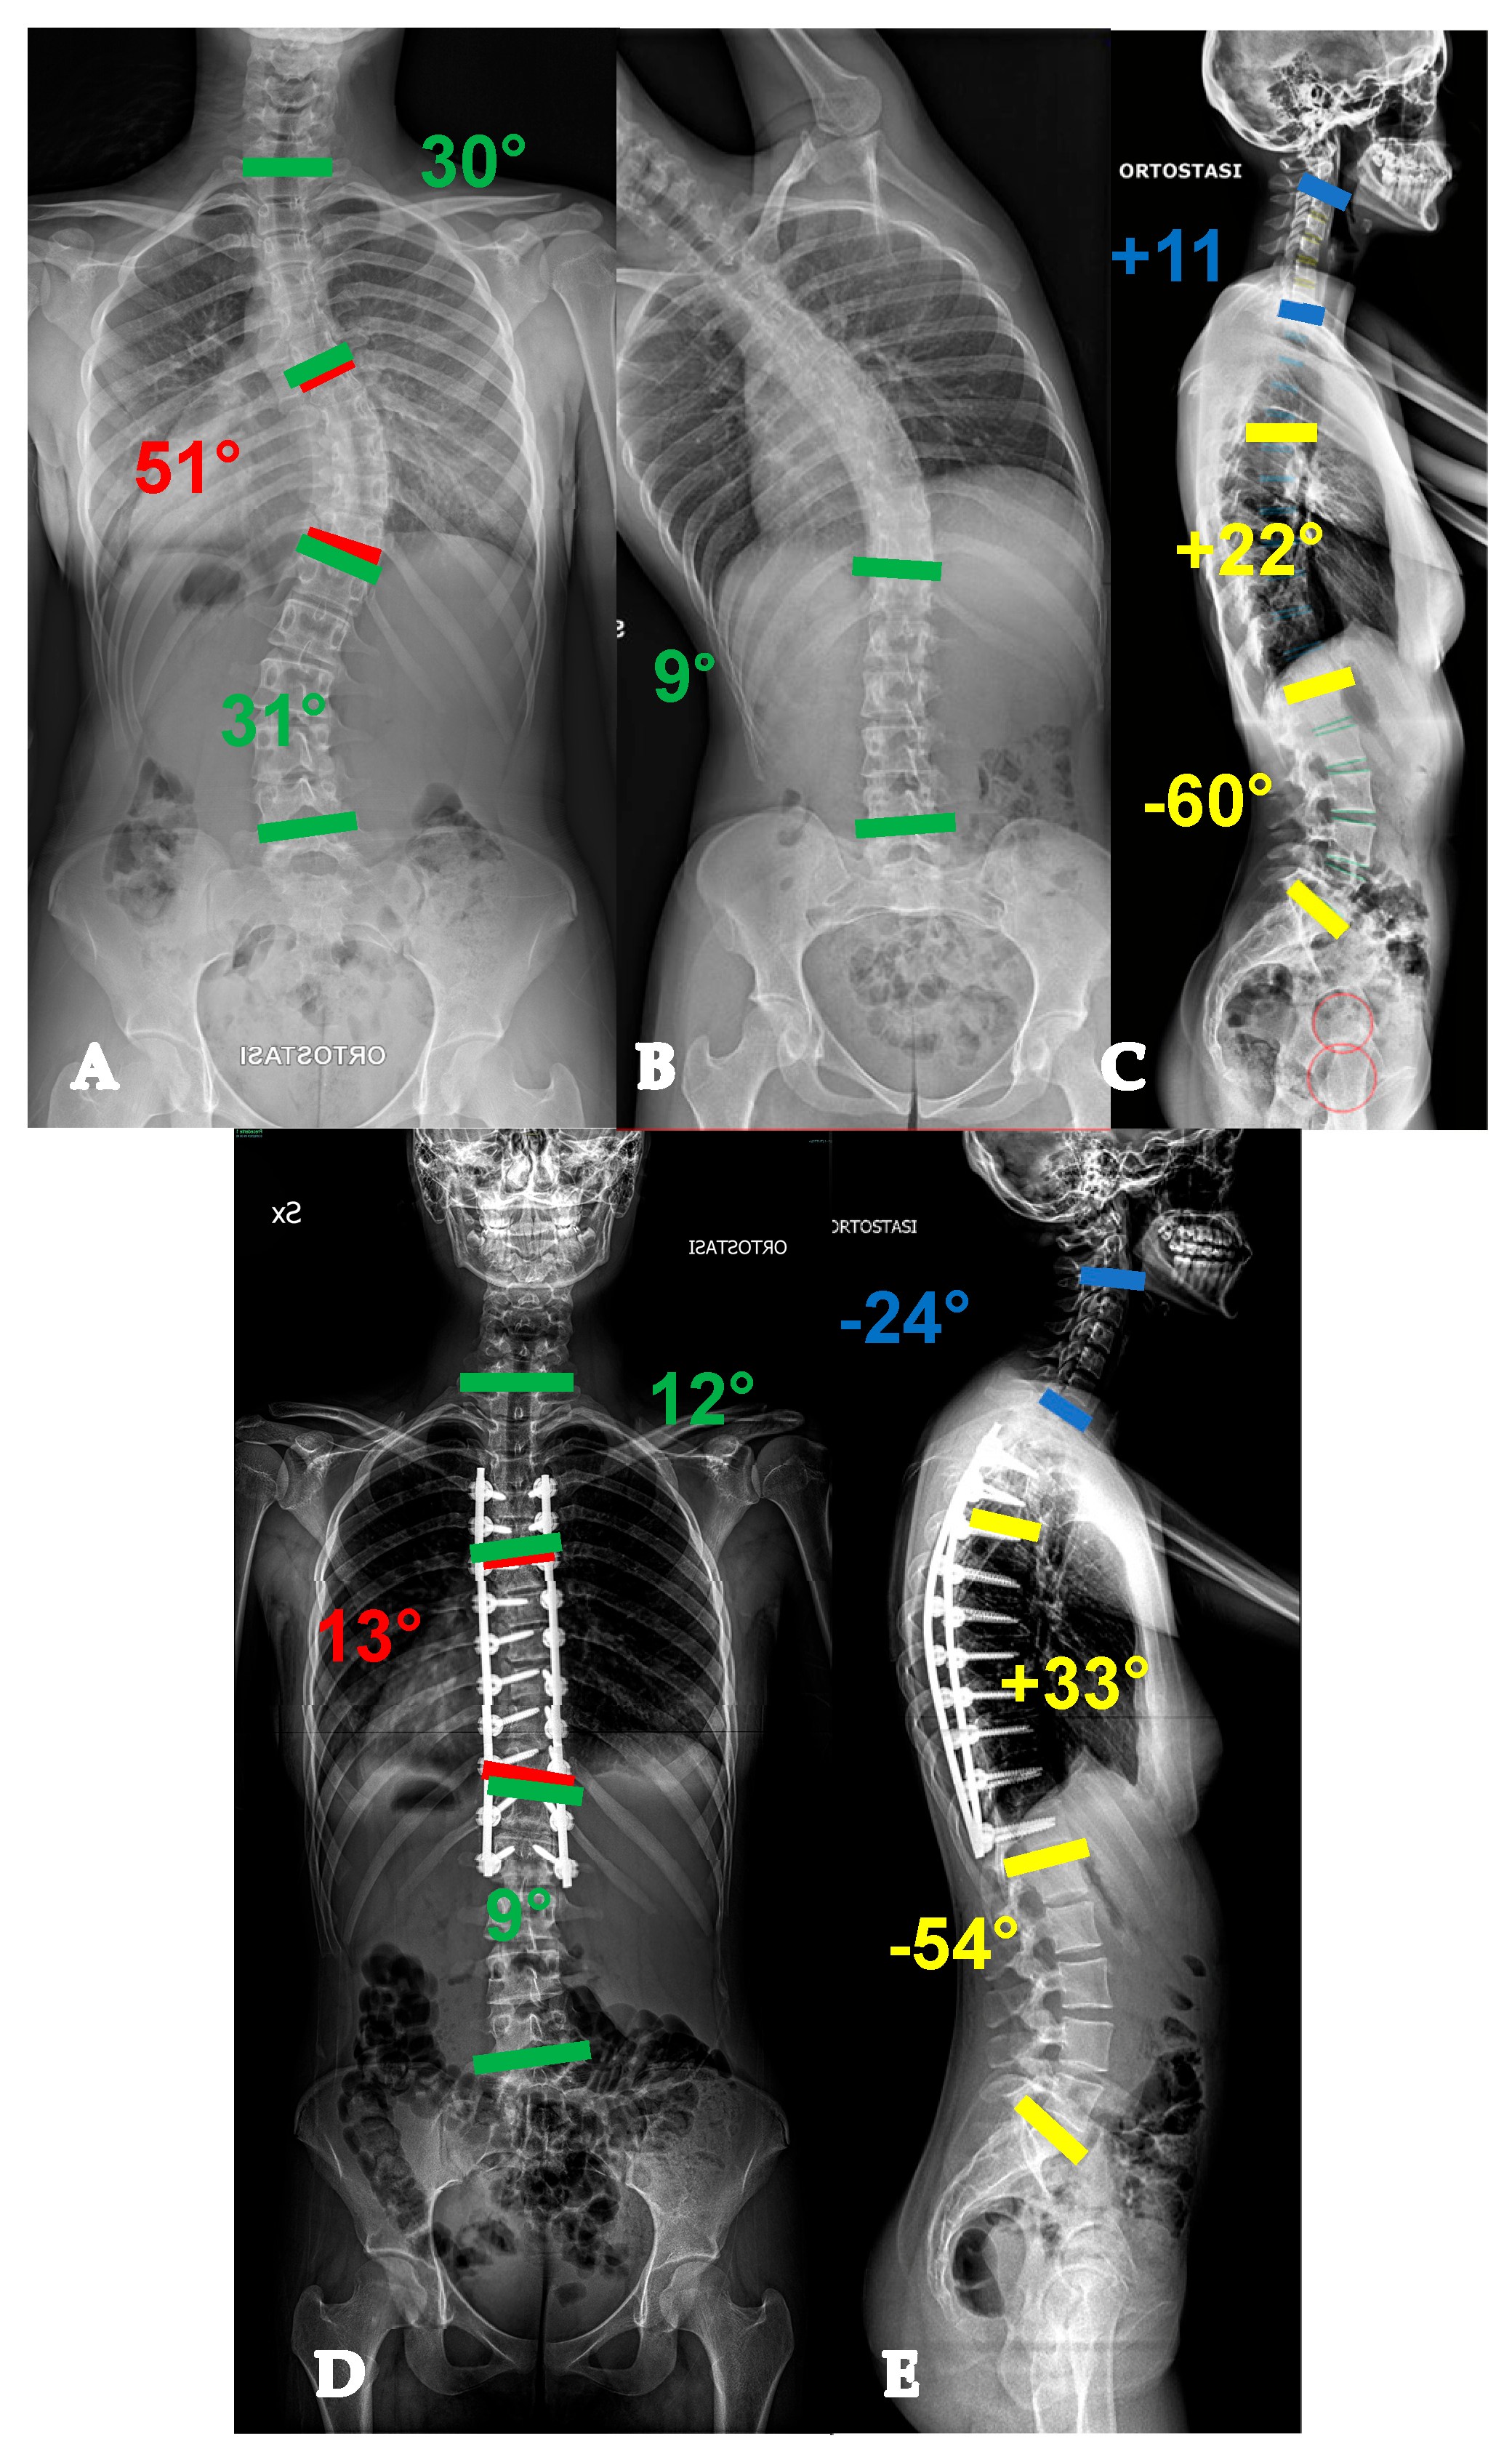

- For curves < 90° OR ≥90° and with a flexibility index > 15% (YADIS 2A), a combination of strategies with an all-posterior approach, already published by the authors under the acronym HiPoAD (High-Density Pedicle Screws, Ponte Osteotomies, Asymmetric Rods Contouring, Direct Vertebral Rotation) [10], may be sufficient to address the deformity. In particular, high-density constructs are preferrable in order to dissipate the corrective forces on every level and decrease the pull-out risks. Then, an aggressive posterior release based on multiple asymmetric Ponte osteotomies is of paramount importance, in order to allow an optimal deroto-translation over two asymmetrically contoured rods (Figure 3) [10,11].

- For curves ≥ 90° AND with a flexibility index < 15% (YADIS 2B), the HiPoAD technique, even though it proved to be effective for this kind of curve when addressed during adolescent years [12], may not be powerful enough for YAdIS 2 patients. These cases should be addressed with a three-columnar approach. One strategy could be to adopt three-column osteotomies like VCR. A possible alternative, in order to avoid the risks of a three-column osteotomy, is to perform a three-columnar release through a combined approach: an anterior thoracoscopic release (wide resection of anterior longitudinal ligament and multiple periapical discectomies), followed by a posterior column release based on multiple Ponte Osteotomies and a posterior correction (VT-HiPoAD, Videothoracoscopic release—HiPoAD) (Figure 4).